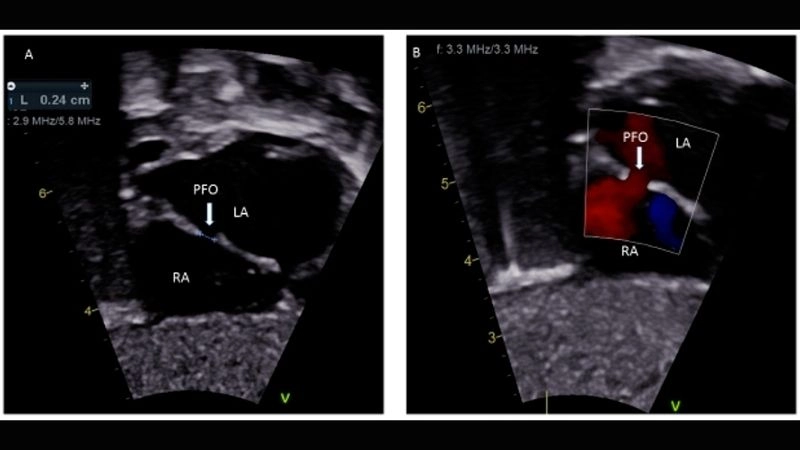

Images visual examples of patent foramen ovale (PFO)

Patent foramen ovale is a heart condition where a small flap-like opening between the left and right atria fails to close after birth. Visual examples often show its location within the atrial septum and how blood flow may bypass normal circulation.

PFO diagnosis tests to detect hidden heart condition